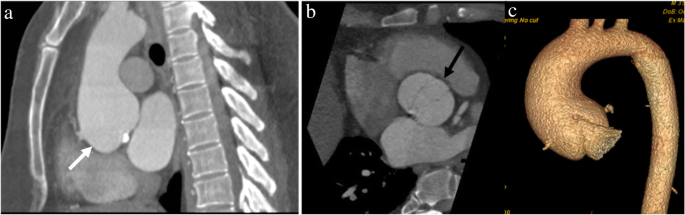

A 43-year-old man with Marfan syndrome and bicuspid aortic valve: sagittal (a) and axial (b) CTA images shows aortic root aneurysm with dilatation centered at the sinuses of Valsalva (white arrow in a) with effacement of the sinotubular junction and normal caliber ascending aorta and bicuspid aortic valve (black arrow in b). A “tulip-shaped” configuration of the aortic root is better appreciated on the volume rendered image (c)

A 41-year-old-man with incidentally detected sinus of Valsalva aneurysm. Non-contrast chest CT (a) obtained as a work-up for fever showed an incidental dilatation (white arrow) of the aortic root (CT was done with high pitch, enabling the anatomic evaluation of aortic root despite the lack of ECG gating). Follow-up contrast-enhanced-gated CTA images (b and c) showing an incidental aneurysm of the noncoronary sinus of Valsalva (black arrow)